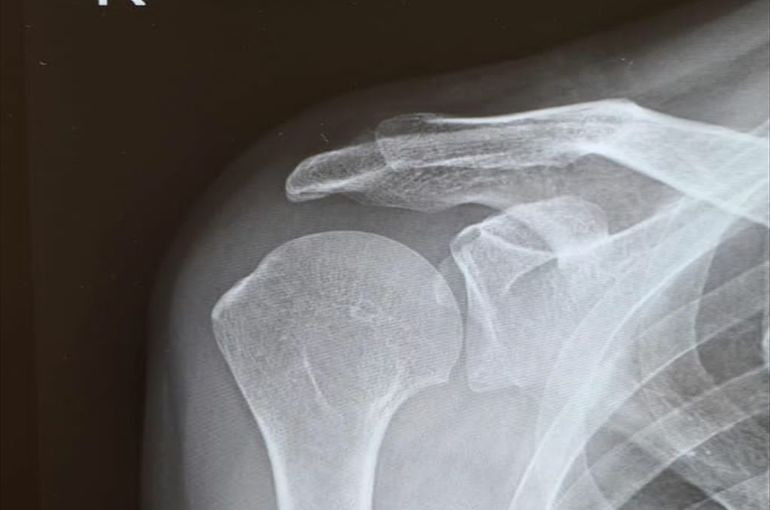

整形外科はレントゲンやCT,MRI等で

身体の中を調べて

原因箇所を調べることができます。

整形外科で検査をする

一番のメリットは、

四十肩/五十肩と似た症状の

『腱板損傷』や『腱板断裂』を

見極めることが出来る、

これにつきます。